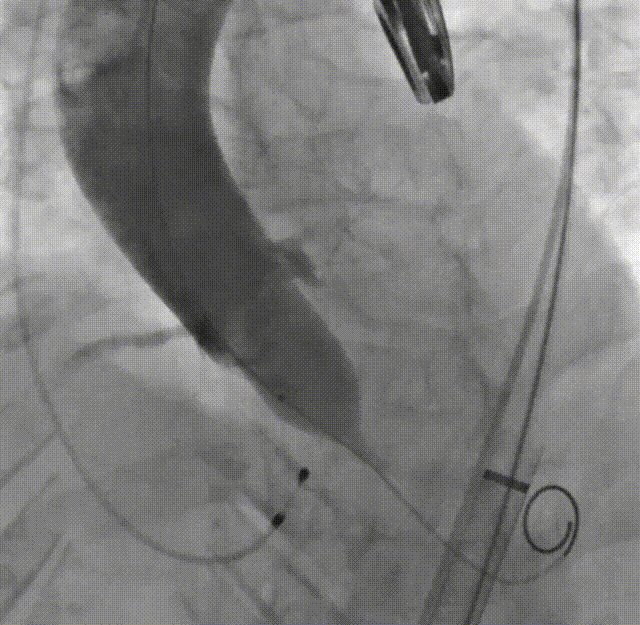

右侧主入路造影

左侧辅入路造影

主动脉根部造影